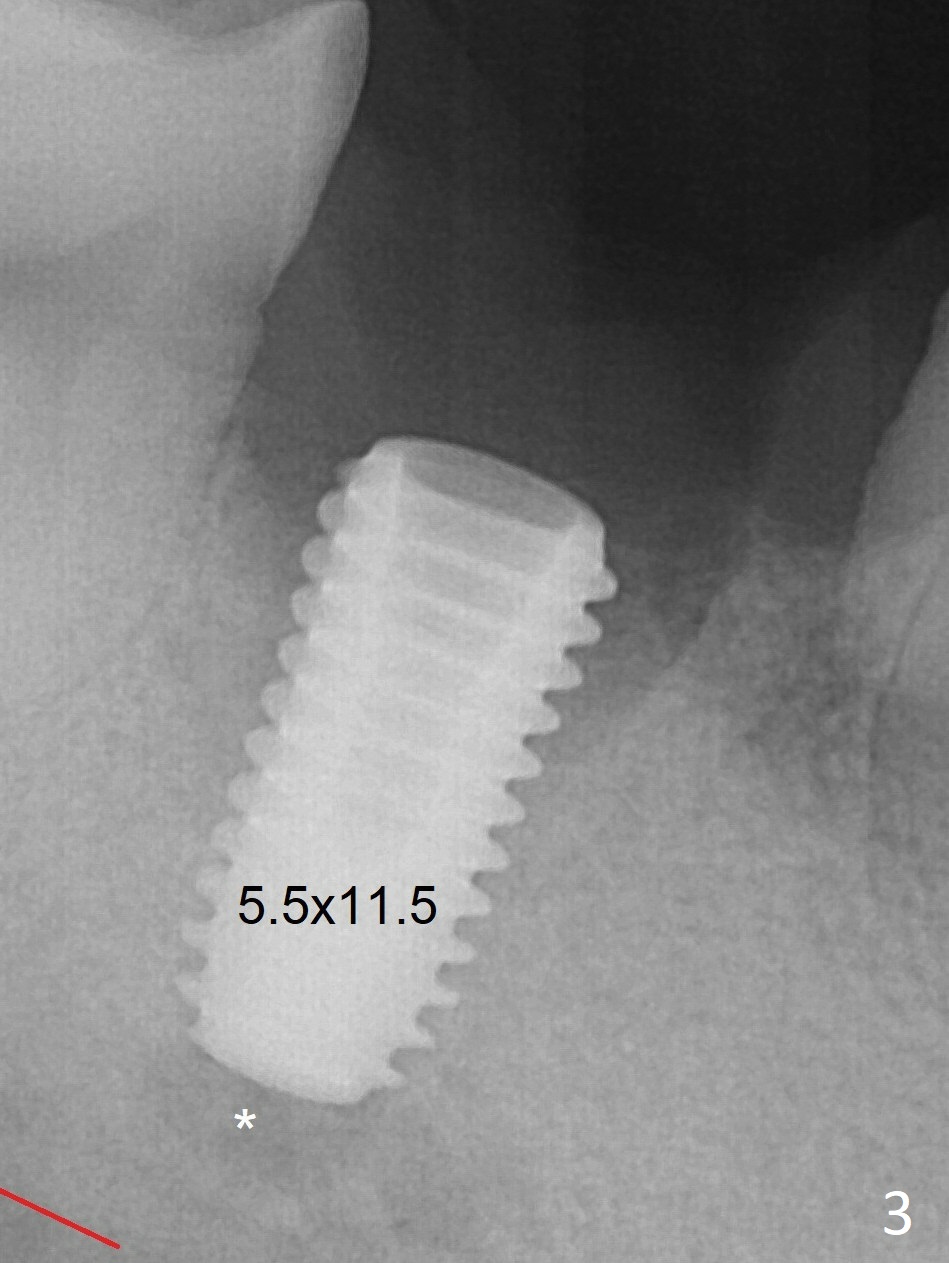

Following 4.8 mm drill, a 5.5x11.5 mm implant is placed initially (Fig.3) with an apical space (*) and clearance between the osteotomy and the Inferior Alveolar Canal (red dashed line). The implant is placed deeper with placement of a 6.5x4(5) mm abutment and bone graft (*, Fig.4). There is no bone loss 3.5 months postop (Fig.8). The abutment margin is lowered by prep before impression. In fact the abutment has not been seated completely since its placement (Fig.4,5,8).